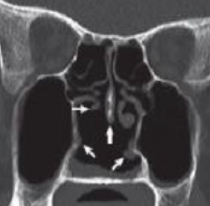

A full ANCA profile can be used in diagnosing

severe active GPA and MPA.

Biopsy is another supportive tool that can be confirmatory, particularly in cases with renal, pulmonary, or skin involvement, but treatment should not necessarily be delayed simply to get a biopsy.